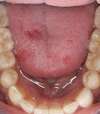

Les empreintes numériques : la précision au service du sourire

Les empreintes numériques remplacent désormais les empreintes traditionnelles, souvent source d’inconfort. Grâce au scanner intra-oral, les dents sont enregistrées en quelques secondes sous forme d’images 3D haute définition. Cette technique offre une précision incomparable et élimine les imprécisions liées aux matériaux d’empreinte classiques. Comme les données sont visualisées instantanément, il devient possible de corriger les zones manquantes en un seul geste et de garantir une exactitude optimale dès la première prise. Cette finesse de reproduction se traduit par des restaurations mieux ajustées, une pose plus simple et une réduction notable des retouches. Par ailleurs, la transmission numérique immédiate accélère l’ensemble du processus, ce qui permet d’obtenir des traitements plus rapides et mieux maîtrisés.